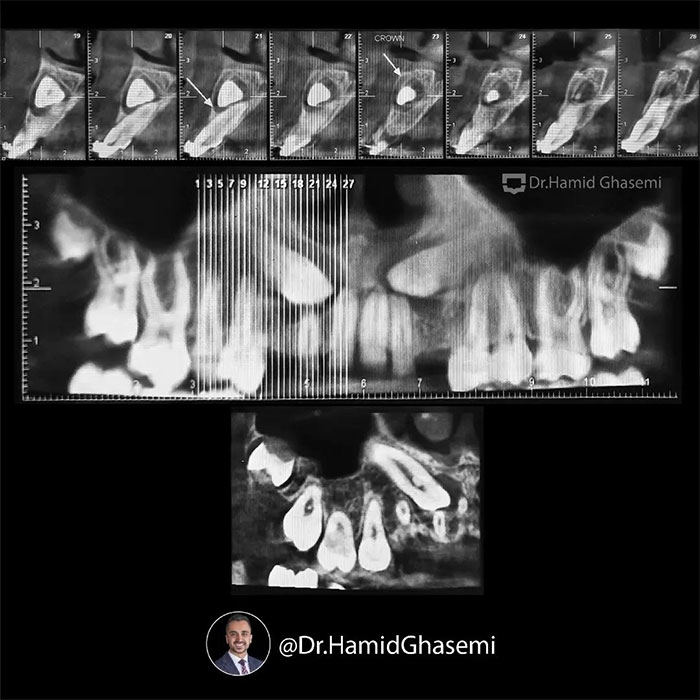

یک کیس خیلی جالب با مشکل جلوزدگی متوسط فک بالا و پایین (Bimaxillary dentoalveolar protrusion ) همراه با نهفتگی دوطرفه دندانهای نیش فک بالا. درمان با کشیدن دندان های نیش نهفته فک بالا و دندانهای پرمولر اول پایین انجام شد. تغییرات مثبت و قابل توجه در پروفایل و حالت لبهای بیمار پس از درمان و کسب اکلوژن کلاس ۱ ایده آل همچنان که دندانهای پرمولر اول بالا جایگزین دندانهای نیش نهفته در فک بالا شدند کاملا مشهود است.

This was such an amazing case with moderate bimaxillary dentoalveolar protrusion plus impacted bilateral upper canines. The case was treated by extraction of upper impacted canines and lower 1st premolars. Significant profile change achieved while upper 1st premolars substituted for upper canines properly with a solid perfect class 1 dental occlusion.